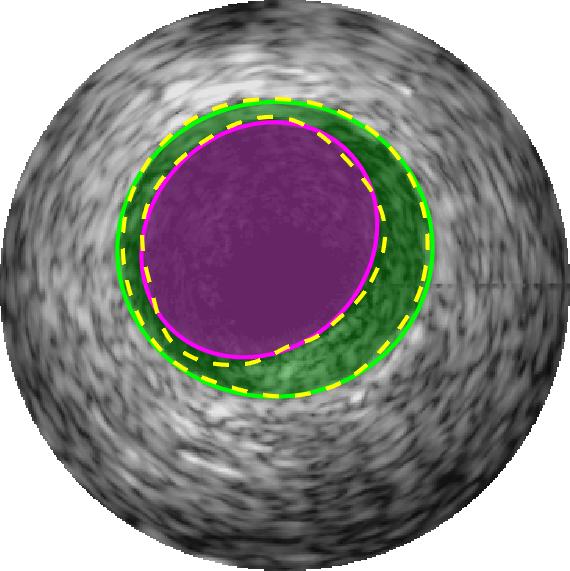

Qualitative evaluations are illustrated in Figure 4 and show the successful segmentation results of the proposed EREL selection strategy for 20 IVUS frames. The lumen areas are highlighted by the magenta colour while the media regions are green. Also, the manually annotated contours for both lumen and media are drawn as yellow dashed lines. As we can see, the chosen frames contain a variety of lumen and media morphologies.